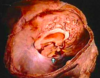

What type of herniation is depicted? Uncal Central (transtentorial) Cingulate (Subfalcine) Transcalvarial Upward cerebellar (transtentorial) Downward cerebellar (Tonsillar)

What type of herniation is depicted? **Uncal** Central (transtentorial) Cingulate (Subfalcine) Transcalvarial Upward cerebellar (transtentorial) Downward cerebellar (Tonsillar) Uncal herniation. Arrows point to the medial temporal lobe that has herniated through the tentorial incisura to compress the midbrain